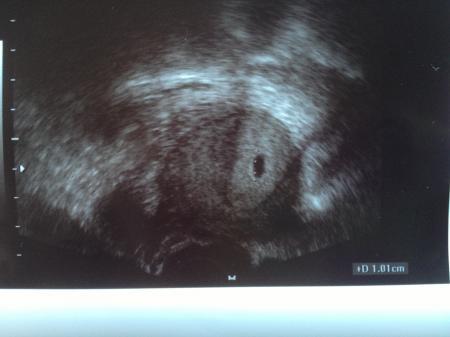

Danke für eure Daumen! Also bei mit ist alles perfekt und zeitgerecht entwickelt! Man sah heute eine fruchthöhle und mein Fa war sichtlich stolz auf "sein" Werk!

Ach und das Foto dazu

Ähm, kann das sein das da 2! Minipünktchen drin sind?? oder seh ich Gespenster??

Jetzt musste ich grad das Bild aufmachen und gucken was du da gesehen hast...

Aber: das sieht man auf dem Bild blos ganz schlecht...da ist ne gepunktete Linie mit der er die fruchtblase gemessen hat...

Also keine Ahnung ob es zwei werden aber gesehen hat man noch nichts von den kleinen krümeln

dann sind das wohl doch nur die Messpunkte ;-)